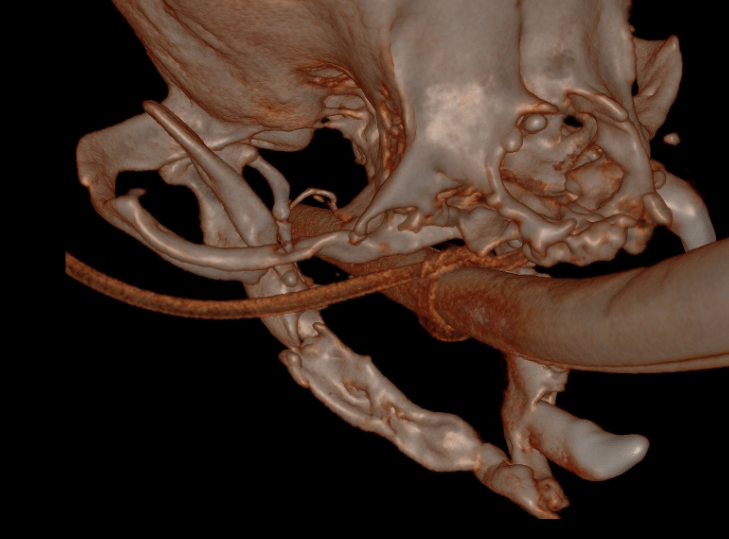

(Hover over image to read caption)

Demonstrates fracture site mobility before surgery

While the mandibles are now much shorter, they are approximately 1cm shorter than the maxilla allowing for function to remain and still have a relatively cosmetic outcome.